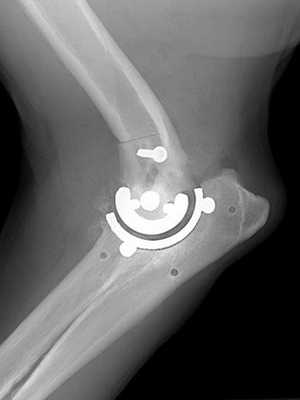

С нашей точки зрения, для сохранения целостности анато- мических структур в области наружного и внутреннего надмыщелков ДОПК целесообразно выполнение их остеотомии, что в дальнейшем позволит более анатомично рефиксировать их к конструкции эндопротеза. Остеотомия выполняется острым тонким долотом или осциллирующей пилой на расстоянии 5−10 мм от верхушки надмыщелка (рис. 2).

После выполнения остеотомии надмыщелков ДОПК общие точки прикрепления мышц остаются фиксированными на костном фрагменте и прошиваются лигатурами для более удобной их мобилизации. Затем выполняется подготовка ложа суставных поверхностей и костномозгового канала плечевого компонента и компонента предплечья эндопротеза. После установки эндопротеза выполняется рефиксация мышц в области наружного и внутреннего «надмыщелков» конструкции (рис. 3). При этом необходимо обратить внимание на ориентацию оси вращения ЛС, что осуществляется выполнением рентгенологических снимков в двух взаимноперпендикулярных проекциях.